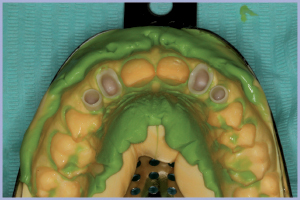

A distanza di 3 mesi dal posizionamento implantare si procedeva alla rimozione dei manufatti provvisori (monconi temporanei con relativa corona e corone provvisorie a livello degli incisivi laterali) ed alla rilevazione di una impronta degli impianti e dei monconi naturali (Figg. 21-22).

I successivi passaggi portavano all’allestimento dei manufatti definitivi in zirconia-ceramica. In particolare venivano allestite tramite procedura CAD-CAM delle cappette in zirconia da incollare sui monconi per ottenerne una individualizzazione estetica; sempre con procedura CAD-CAM si ottenevano le strutture in zirconia successivamente ceramizzate per ottenere i manufatti definitivi (Figg. 23-25).

- Fig. 25 – Impronta di posizione delle cappette in zirconia